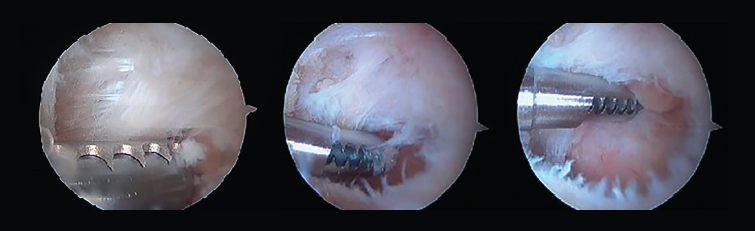

Tras la disección completa del PPA y la evaluación y el tratamiento de la patología asociada del FHL, si es necesario, podemos iniciar el procedimiento de resección ósea(11,12,13). Así, en caso de pinzamiento óseo, los procedimientos se realizan de acuerdo con la etiología de este (Figuras 8 A, B y C).

Figura 8. A: en una primera opción, se realiza la resección ósea mediante un osteotomo de 5 mm; B y C: la segunda opción es realizar la resección mediante el uso de una fresa artroscópica.

En ocasiones, está desprendido y se puede retirar fácilmente con una pinza grasper. Pero, si está fijado por fibrosis, es posible separarlo mediante el empleo de un desperiostizador o el sinoviotomo. Pero, cuando la fusión está calcificada, será preciso emplear un osteotomo de 5 mm introducido por el portal artroscópico. El fragmento escindido se extrae mediante una pinza grasper. También se puede utilizar un terminal de fresado para hacer la resección o para finalizarla regularizando los bordes del hueso. El límite del cartílago de la articulación subastragalina constituye el mejor punto de referencia para asegurarnos una resección adecuada (Figura 9).

Proceso posterolateral del astrágalo hipertrófico o proceso de Stieda

En los casos de PPAH, el hueso se puede cortar mediante el empleo de un osteotomo de 5 mm introducido por el portal artroscópico o resecarse mediante un terminal motorizado de fresa artroscópica. El uso del osteotomo no es fácil debido a que el ángulo del corte no es perpendicular; por ello, la mayoría de las veces es necesario finalizar la resección ósea mediante la fresa de artroscopia.